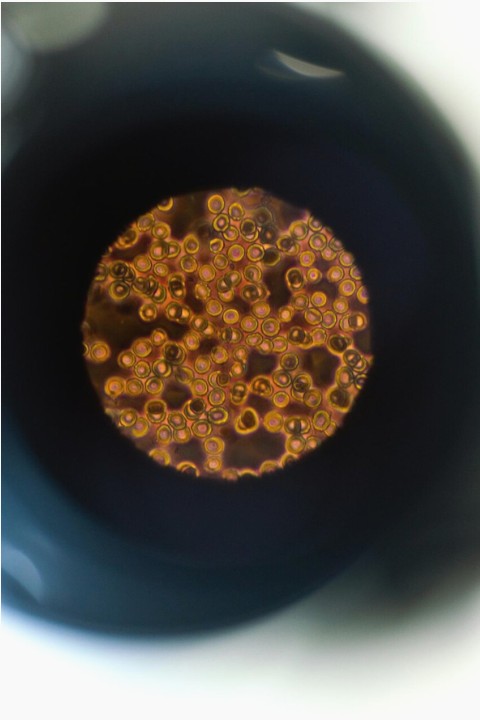

Showcase gallery